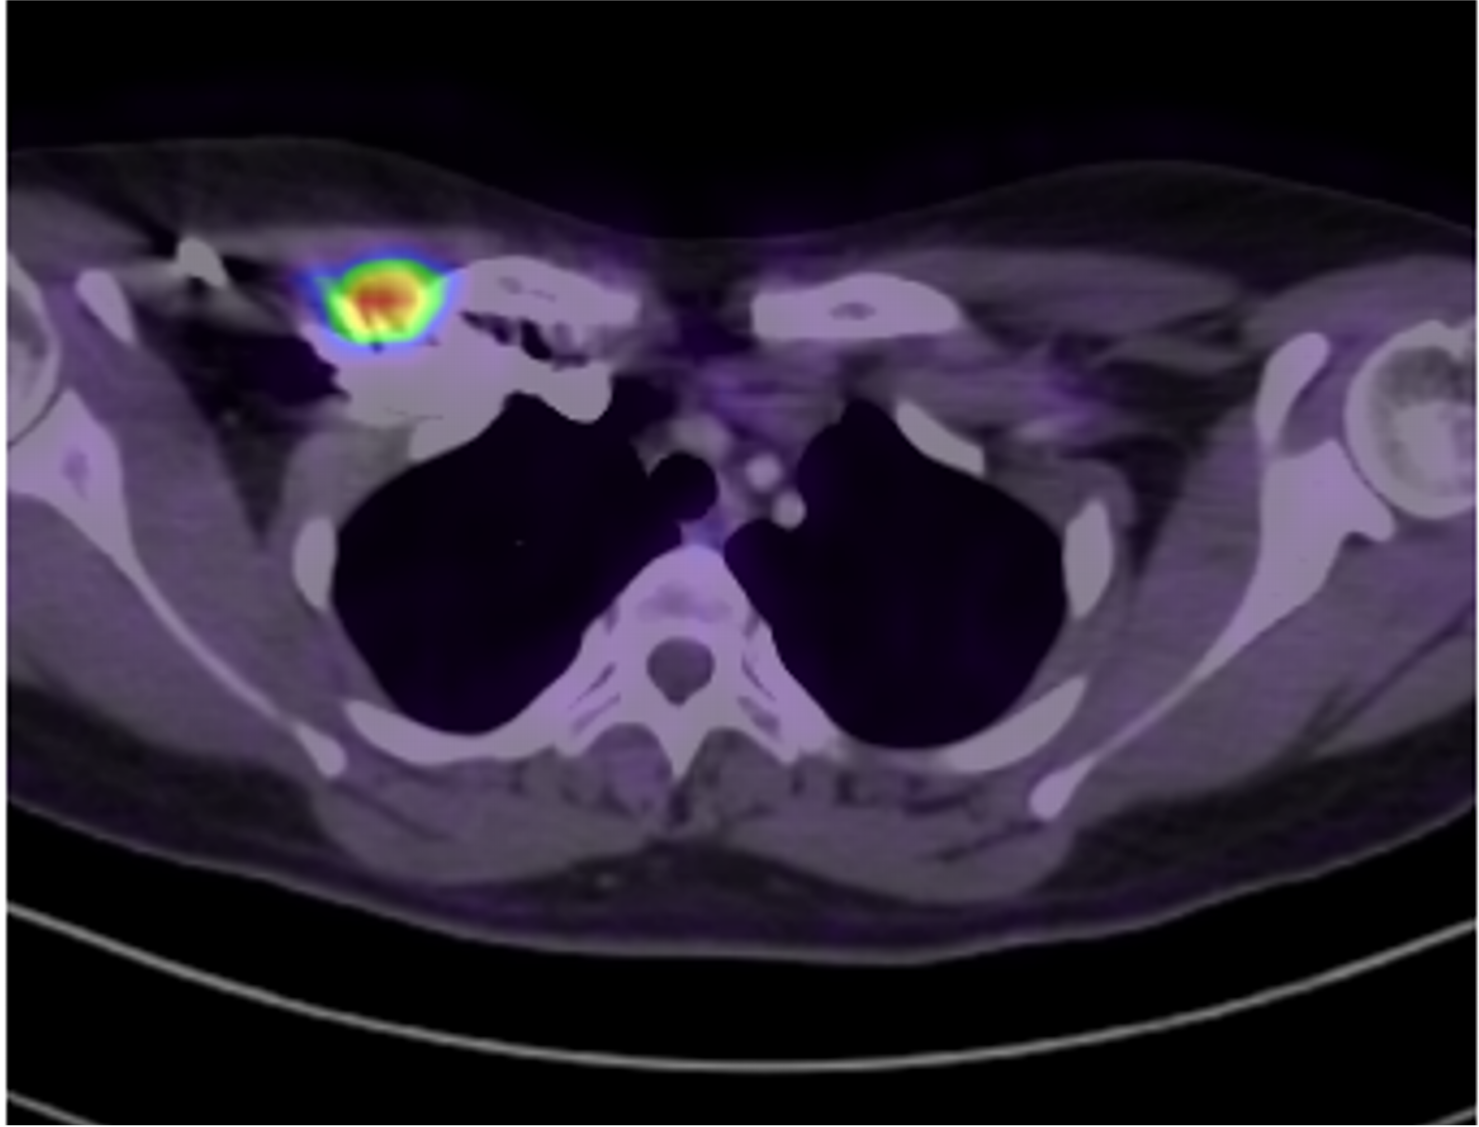

Imágenes de tomografía en adquisición axial en ventana para tejido blando, fase venosa, con su correspondiente correlación con imágenes de PET CT.

J, K Ganglio subclavio derecho con pérdida de su morfología e hilio graso, con eje corto de hasta 10 mm, con hipermetabolismo

I. Imagen de PET CT con adenopatías axilares bilaterales asociadas con hipermetabolismo.